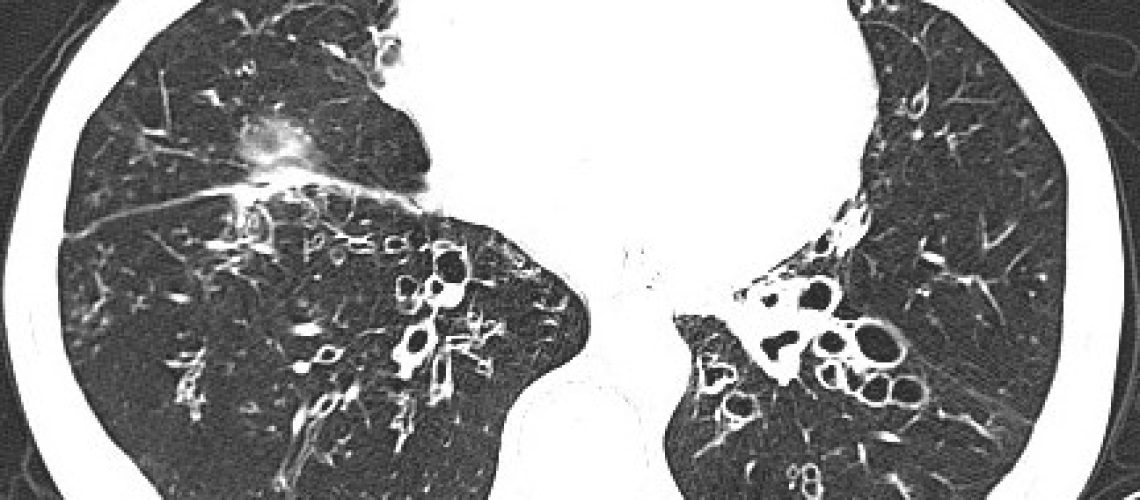

Las bronquiectasias son dilataciones anómalas e irreversibles de los bronquios cartilaginosos de tamaño mediano, que se acompañan de destrucción de los componentes muscular y elástico de la pared bronquial, generalmente asociadas a infección crónica.  Son mas frecuentes en mujeres y la prevalencia aumenta con la edad. Pueden ser localizadas o a veces generalizadas en ambos pulmones. La causa mas frecuentes de las mismas son las infecciones (neumonías, tuberculosis…) pero existen múltiples causas como trastornos genéticos y alteraciones en la respuesta inmunitarias que hay que investigar para obtener un diagnóstico correcto. Los síntomas mas frecuentes son la tos y expectoración crónica mucosa o mucopurulenta y con menor frecuencia acompañada de sangre. El diagnóstico de las bronquiectasias se confirma mediante TCAR torácico.